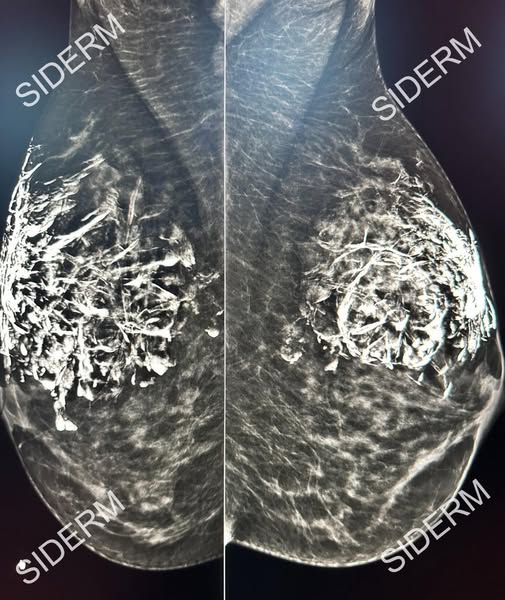

- สิ่งที่อันตรายที่สุดคือ CaHA อาจทำให้เกิดการจับตัวเป็นแคลเซียมในเต้านม ทำให้ภาพจากการตรวจแมมโมแกรม (mammogram) แปลผลได้ยากขึ้น และ บดบังหินปูน (calcification) ที่เป็นสัญญาณสำคัญที่พบในมะเร็งเต้านม

ดังนั้น การฉีด CaHA บริเวณเต้านมจึงไม่ปลอดภัย และส่งผลกระทบต่อการตรวจคัดกรองมะเร็งเต้านมในอนาคตได้ ถือเป็นอันตรายอย่างยิ่ง